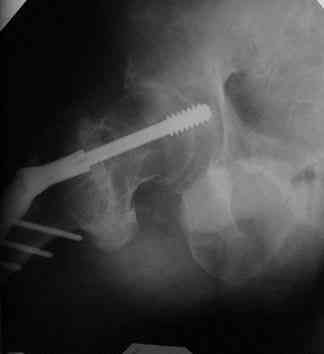

Все-таки хочу поделиться раз затронулась тема, может кому-нибудь и сгодиться. Это пример из области скорее трудноудаляемой. Пациент 50 лет, травма (низкоэнергетическая) 1,5 года назад. Оперирован через неделю (винт отечественный). Через 4 месяца выполнен контрольный снимок, сразу же возник вопрос: почему винт не телескопировался? Вопрос в общем-то так и остался без ответа.

При удалении (наркоз) после неимоверных усилий пришлось выкрутить фиксатор единым блоком и только тут все встало на свои места. См. фото.